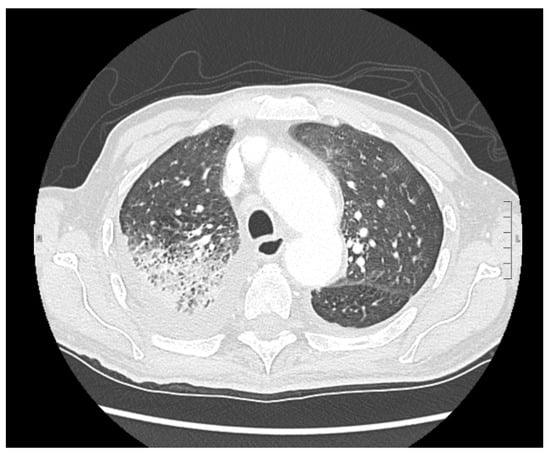

2. Case Presentation